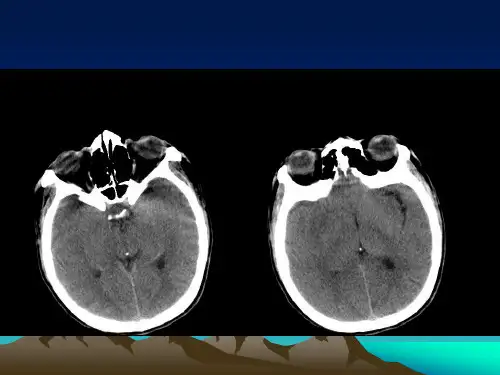

辅查:MRI示颅内占位.诊断:颅内占位/动脉瘤?左额颞胶质瘤?现为入院第二日。

3.辅助检查:头颅MRI提示为“颅内占位”。